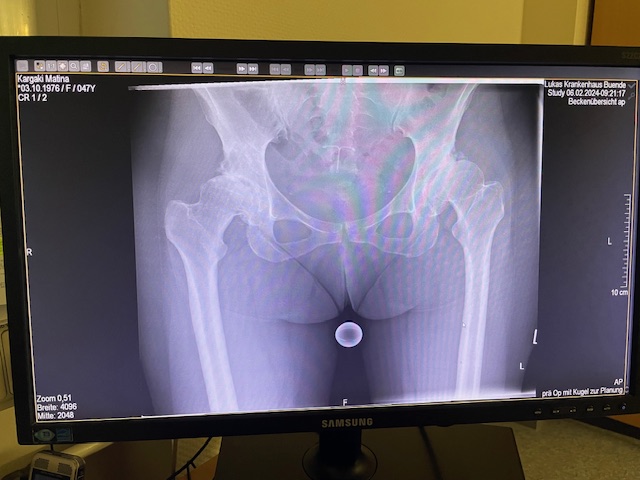

Η ασθενής είχε απευθυνθεί από χρόνια σε πολλούς συναδέλφους ορθοπεδικούς στην Ελλάδα και το εξωτερικό. Είχε προηγηθεί ήδη διεξοδικός απεικονιστικός έλεγχος (ακτινογραφίες λεκάνης και ισχίου, αξονική και μαγνητική τομογραφία).

Το 2024 όταν πλέον η ασθενής απευθύνθηκε σε εμένα, ακολούθησε εκ νέου ακτινογραφικός έλεγχος ώστε να μπορέσει να πραγματοποιηθεί ο προεγχειρητικός ψηφιακός σχεδιασμός του Χειρουργείου.

Ο ακτινογραφικός έλεγχος έδειχνε προχωρημένες εκφυλιστικές αλλοιώσεις και αλλοίωση της ανατομίας της κοτύλης και του μηριαίου.